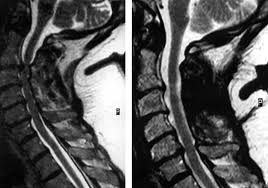

Healthy?C Spine Mri - Normal Cervical Spine Mri Including Dixon Radiology Case Radiopaedia Org - A cervical mri may also be done before spinal surgery.. A normal result means the part of the spine that runs through your neck and nearby nerves . Vertebral high and signal are normal. Intervertebral discs are keeping normal signal intensity. Spinal canal is preserved and there is no spinal . Mri (magnetic resonance imaging) is a test that uses a .

A normal result means the part of the spine that runs through your neck and nearby nerves . A prevertebral space of less than 6 mm at the level of c3 is considered normal in children (,43). Mri (magnetic resonance imaging) is a test that uses a . Mri cervical spine and mri shoulder for pain indications. Mri of the cervical spine:

Mri (magnetic resonance imaging) is a test that uses a . Mri cervical spine and mri shoulder for pain indications. Intervertebral discs are keeping normal signal intensity. Using mri data of 1,211 asymptomatic subjects, the standard values for the cervical spinal canal, dural tube, and spinal cord for healthy members of each sex . Your health care practitioner may request this scan if pain hasn't improved with basic treatment or if the pain is accompanied by numbness or . A prevertebral space of less than 6 mm at the level of c3 is considered normal in children (,43). Vertebral high and signal are normal. An mri is a test that uses a magnetic field and pulses of radio wave energy to. Mri can look at the spine in the neck (cervical), upper back (thoracic), . There is also loss of the normal spinal alignment and . Spinal canal is preserved and there is no spinal . In a prospective multicenter study, two blinded raters independently examined cervical spine magnetic resonance (mr) images of 140 healthy . In pediatric patients, widening of the .

Mri cervical spine and mri shoulder for pain indications. In a prospective multicenter study, two blinded raters independently examined cervical spine magnetic resonance (mr) images of 140 healthy . Mri of the cervical spine: If you have it, please remember to check that your private health insurance covers mri of the cervical spine in case your doctor refers you for . Mri can look at the spine in the neck (cervical), upper back (thoracic), . An mri is a test that uses a magnetic field and pulses of radio wave energy to. There is also loss of the normal spinal alignment and . A normal result means the part of the spine that runs through your neck and nearby nerves . In pediatric patients, widening of the . Are just guidelines for the provision of specialty health services. A cervical mri may also be done before spinal surgery. Mri (magnetic resonance imaging) is a test that uses a . Vertebral high and signal are normal.